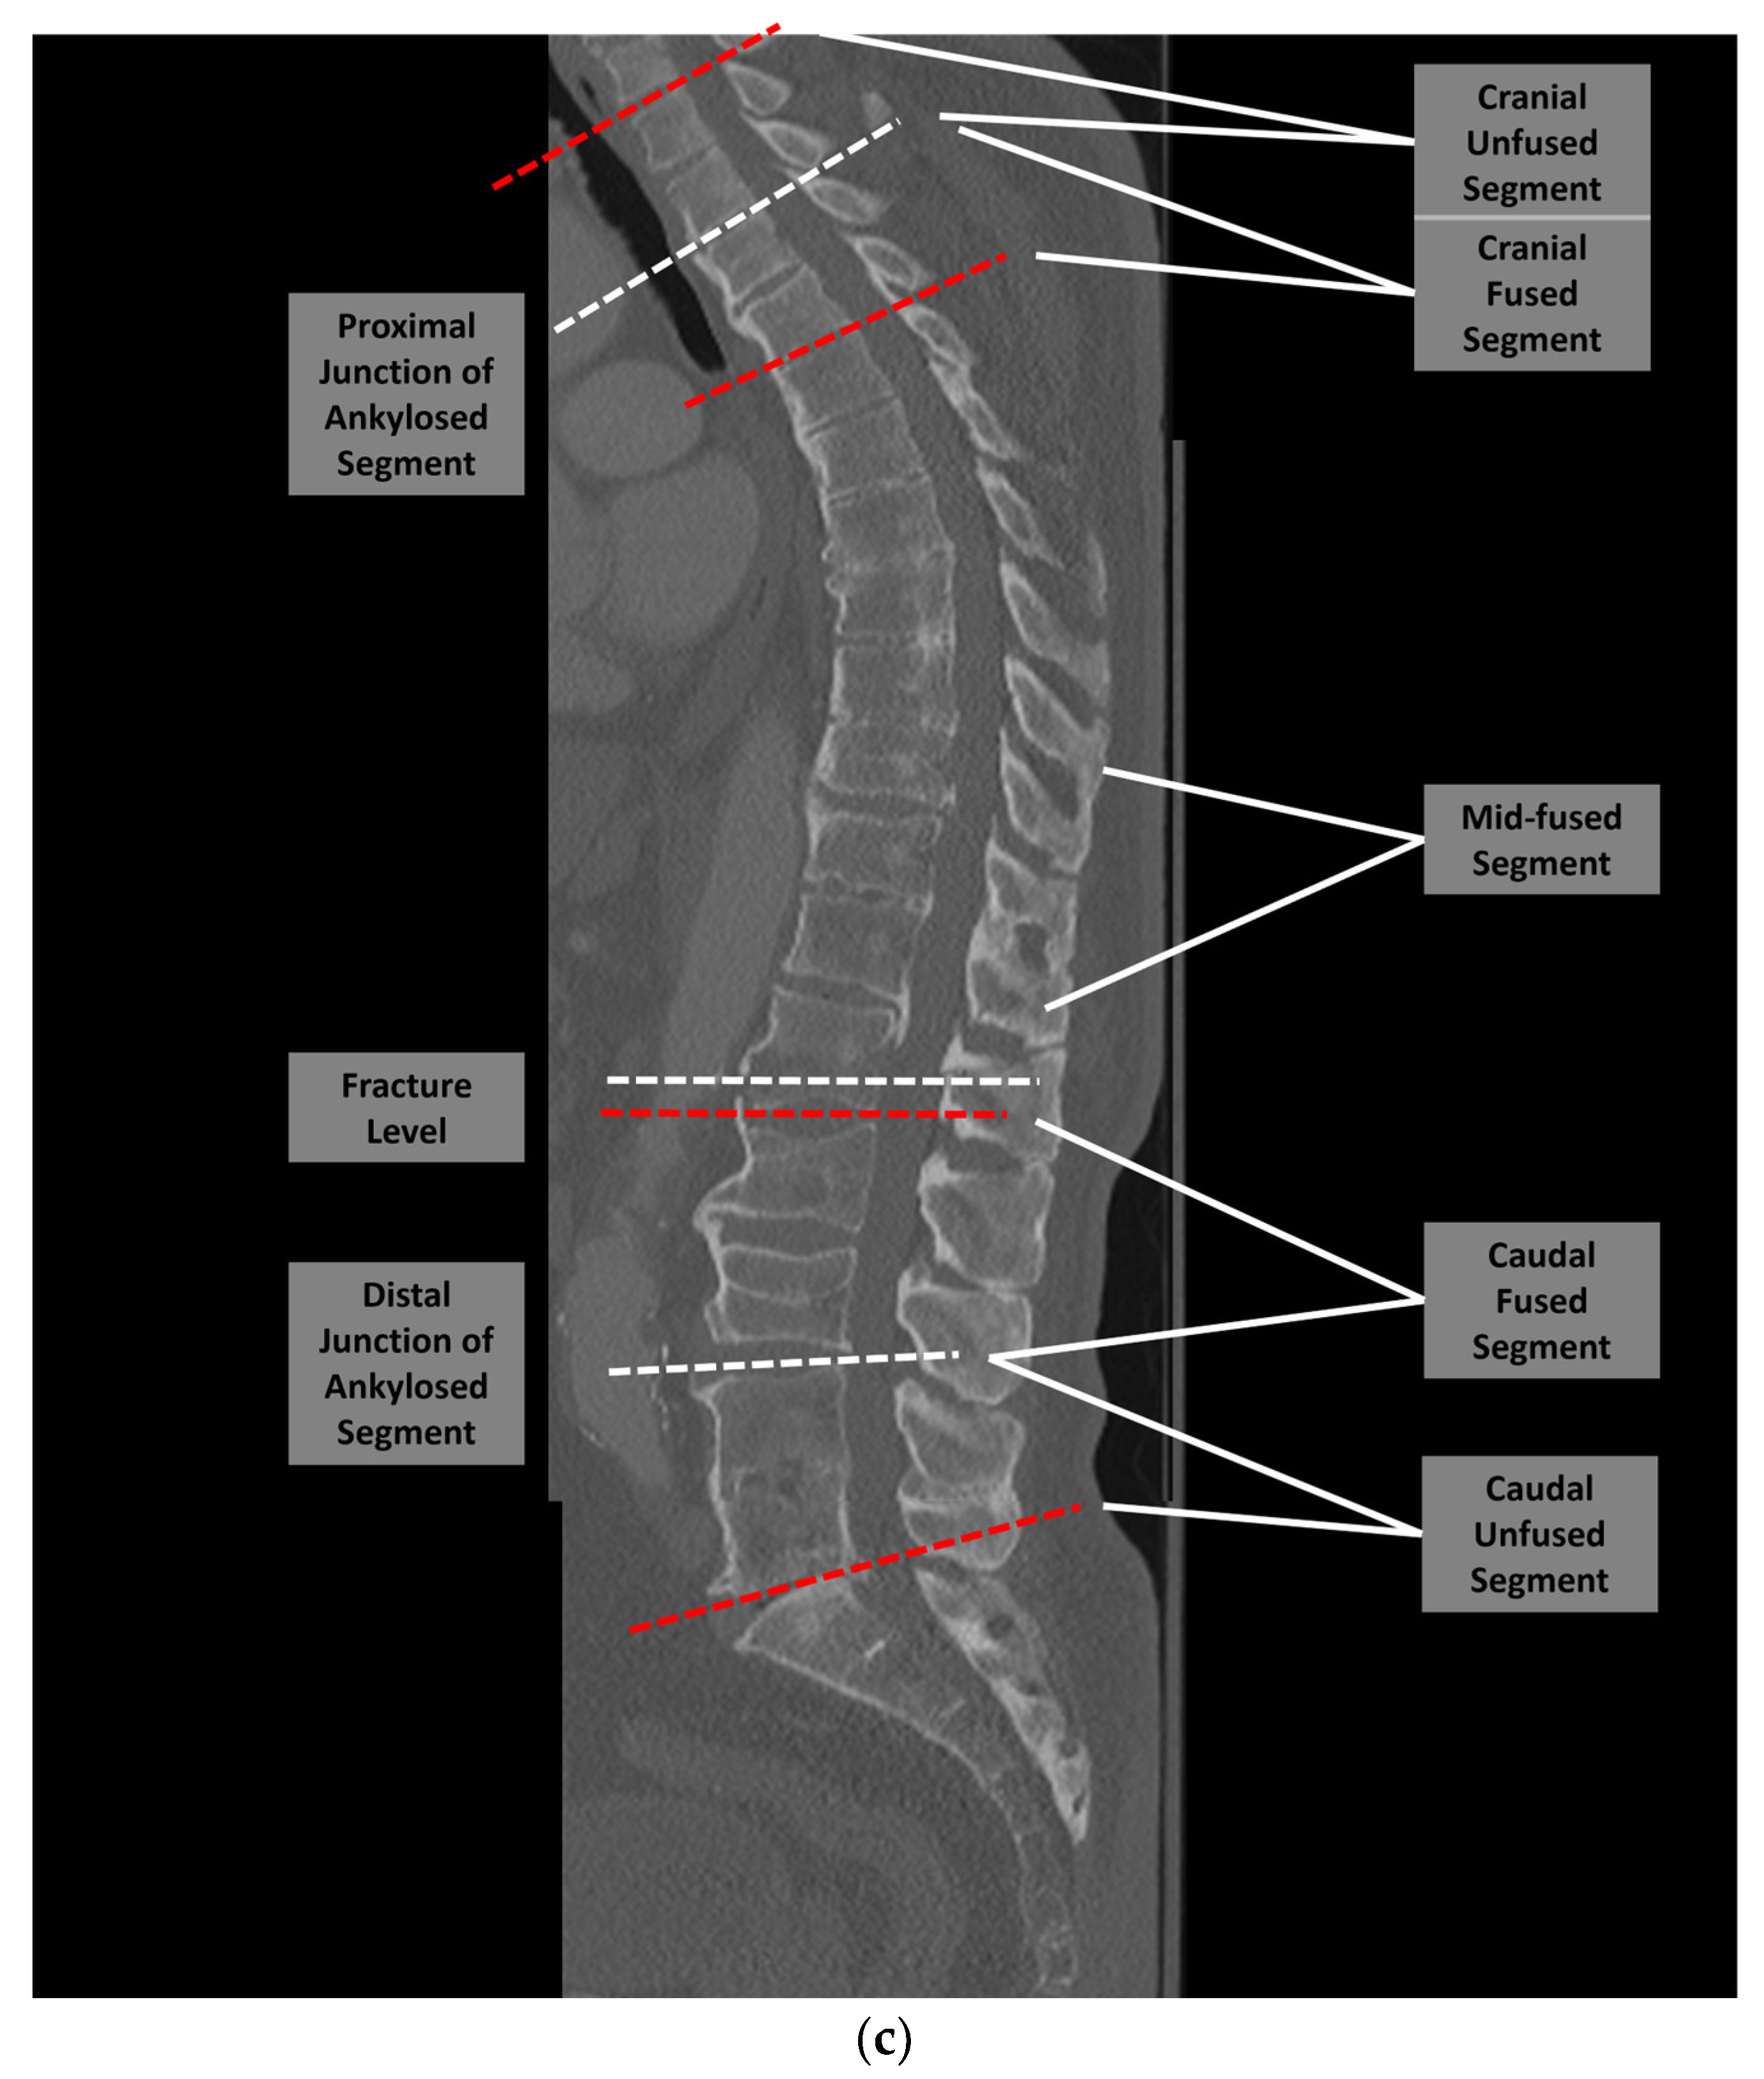

2. Materials and Methods